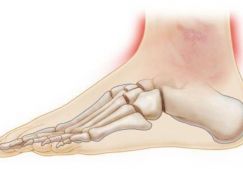

Первым симптомом растяжения мышц коленного или голеностопного сустава является сильная, пронизывающая боль. Она настолько острая, что возможна потеря сознания. Особенно опасен болевой шок — патологическое состояние, угрожающее жизни пострадавшего из-за учащения сердцебиения, резкого падения артериального давления. В момент разрыва волокон может слышаться щелчок, напоминающий хруст переламываемой сухой палки. Раздражение рецепторов, усиление кровотока приводят к покраснению кожи в области повреждения. В течение нескольких часов возникают следующие признаки, характерные для растяжения мышц:

- боль усиливается при попытке опереться на стопу;

- подвижность ноги ограничена;

- формируется подкожная гематома;

- изменяется чувствительность в области повреждения;

- пораженные ткани отечны, нога увеличивается в размере.